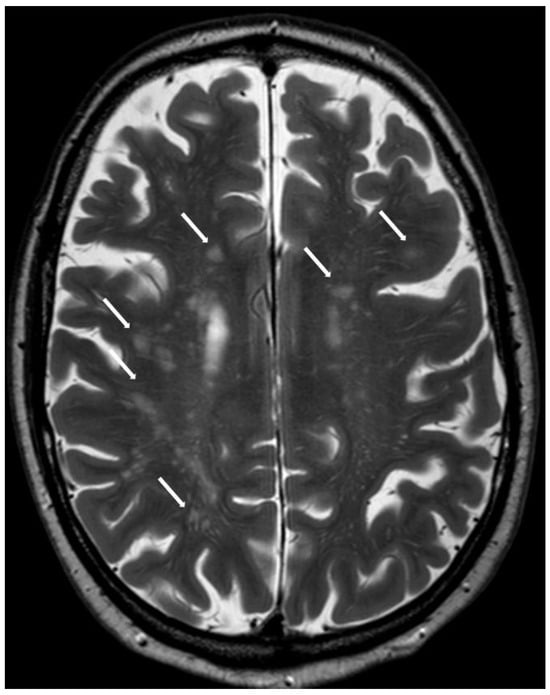

5.2.1. Enlarged Perivascular Spaces

5.2.2. Subcortical White Matter Lesions